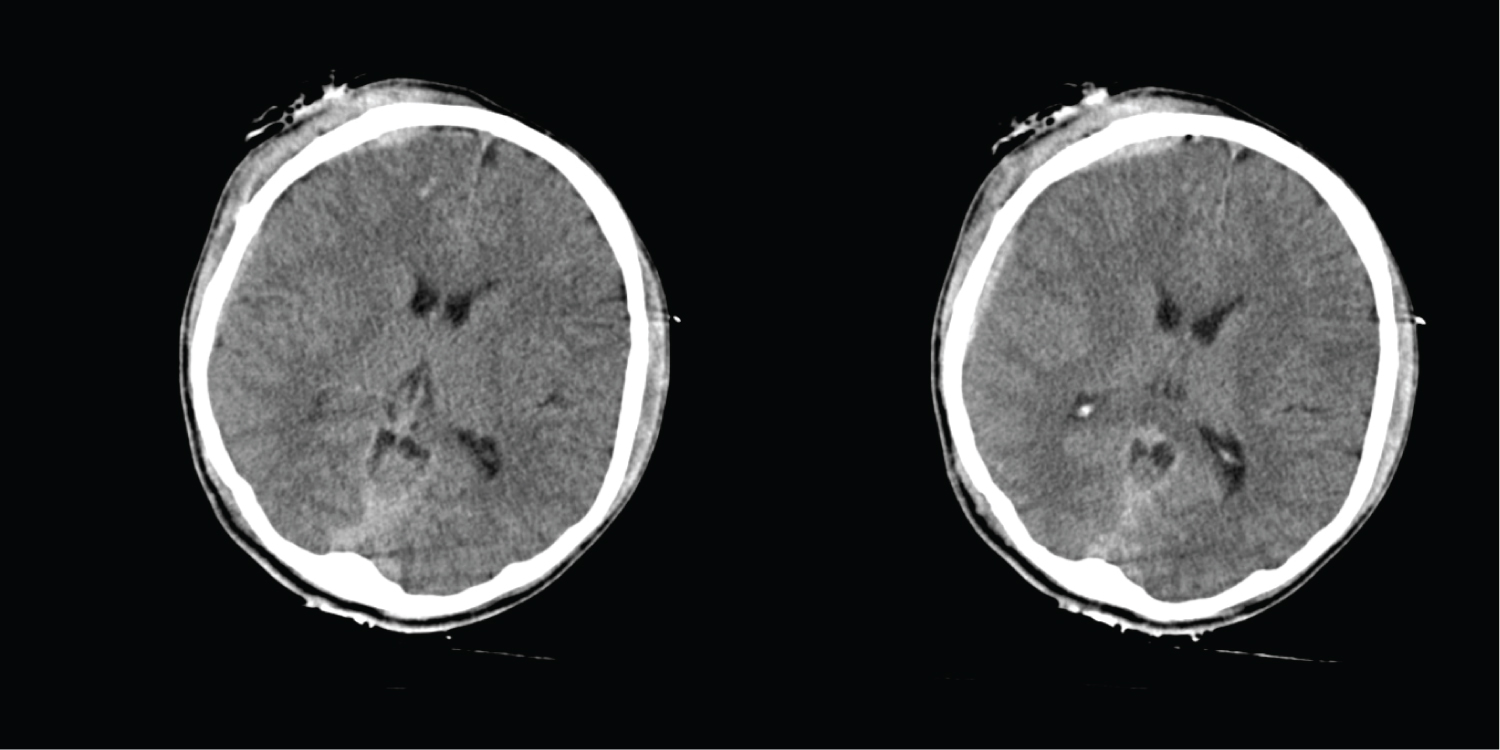

A 17-year-old male presented unconscious after an MVA. On initial assessment, his GCS score was 4/15 (E1V1M2). His blood pressure was 154/90 mmHg, pulse rate was 94/min, respiratory rate was 25/min (tachypnoeic) and oxygen saturation was 100% under room air. Pupils were 4 mm bilaterally and not reactive to light. CT brain scan showed right sided subdural haemorrhage with interhemispheric extension, frontal contusions accompanied with multiple skull fractures. There were also tentorial subdural and traumatic subarachnoid haemorrhages (Figure 2a).

Figure 2a: (Post-trauma Day 1) There is presence of right subdural and subarachnoid bleed at right frontoparietal region. The maximum thickness of the SDH measuring 0.5 cm. There is extension of the bleed into the interhemispheric fissure, cerebellar tentorium and prepontine cistern. Multiple small contusional bleedings in right frontal lobe. There are multiple fractures involving the right frontoparietal skull vault, anterior and posterior wall of right frontal sinus, right lamina papyracea, anterior wall of left sphenoid sinus. View Figure 2a

He was transferred to the general ward and continued on physical and occupational rehabilitation. He developed one episode of generalised seizure that was managed with sodium valproate. A CT brain scan was repeated one month after the head injury which showed resolution of the right subdural hematoma (Figure 2b). Patient was subsequently discharged after one-month stay in hospital. One month after starting NeuroAiD, his GCS score improved to 15/15 (E4V5M6), with improvement in his motor and sensory functions. He was able to tolerate NeuroAiD in capsule form. By the sixth month, his motor score improved from 3/5 to 5/5 on all limbs. He was able to walk independently without assistance. There were no reported adverse events.

Figure 2b: (Post Trauma Month One) The previously seen right subdural and subarachnoid bleedings at right frontoparietal region are no longer seen. View Figure 2b